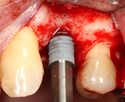

يتم اجراء جراحة الأسنان في العيادة تحت ظروف معقمة، من قبل طبيب أسنان متخصص في زراعة الأسنان و/أو جراحة الفم والفك. يتم تخدير المريض بواسطة حقنة بمخدر موضعي في منطقة دواعم السن، كما هو الحال في علاجات الأسنان العادية (في بعض الأحيان هناك حاجة بتوسيع نطاق التخدير، وفقاً لموقع الغرسات).

اذا كان العظم على استعداد لتلقي الزرع (أحيانا بعد سلسلة علاجات مسبقة)، يمكن البدء بعملية زرع الاسنان. يتم تثبيت المسامير المعدنية اللولبيه براغي، بعظم الفك. في سلسلة اخرى من العلاجات بعد فترة من ادخال البراغي، تبدا عمليات اعادة البناء عن طريق أخذ القياسات وانشاء التاج/الجسر. عندما يدور الحديث عن فترة الانتظار بين تركيب الغرسات وبين تنفيذ الاستبناء النهائي، فان هنالك اكثر من نهج واحد. النهج المتبع غالبا هو الانتظار لمدة 6 أسابيع على الأقل حتى تلتئم الانسجة، وأحيانا تصل فترة الانتظار لعدة شهور.